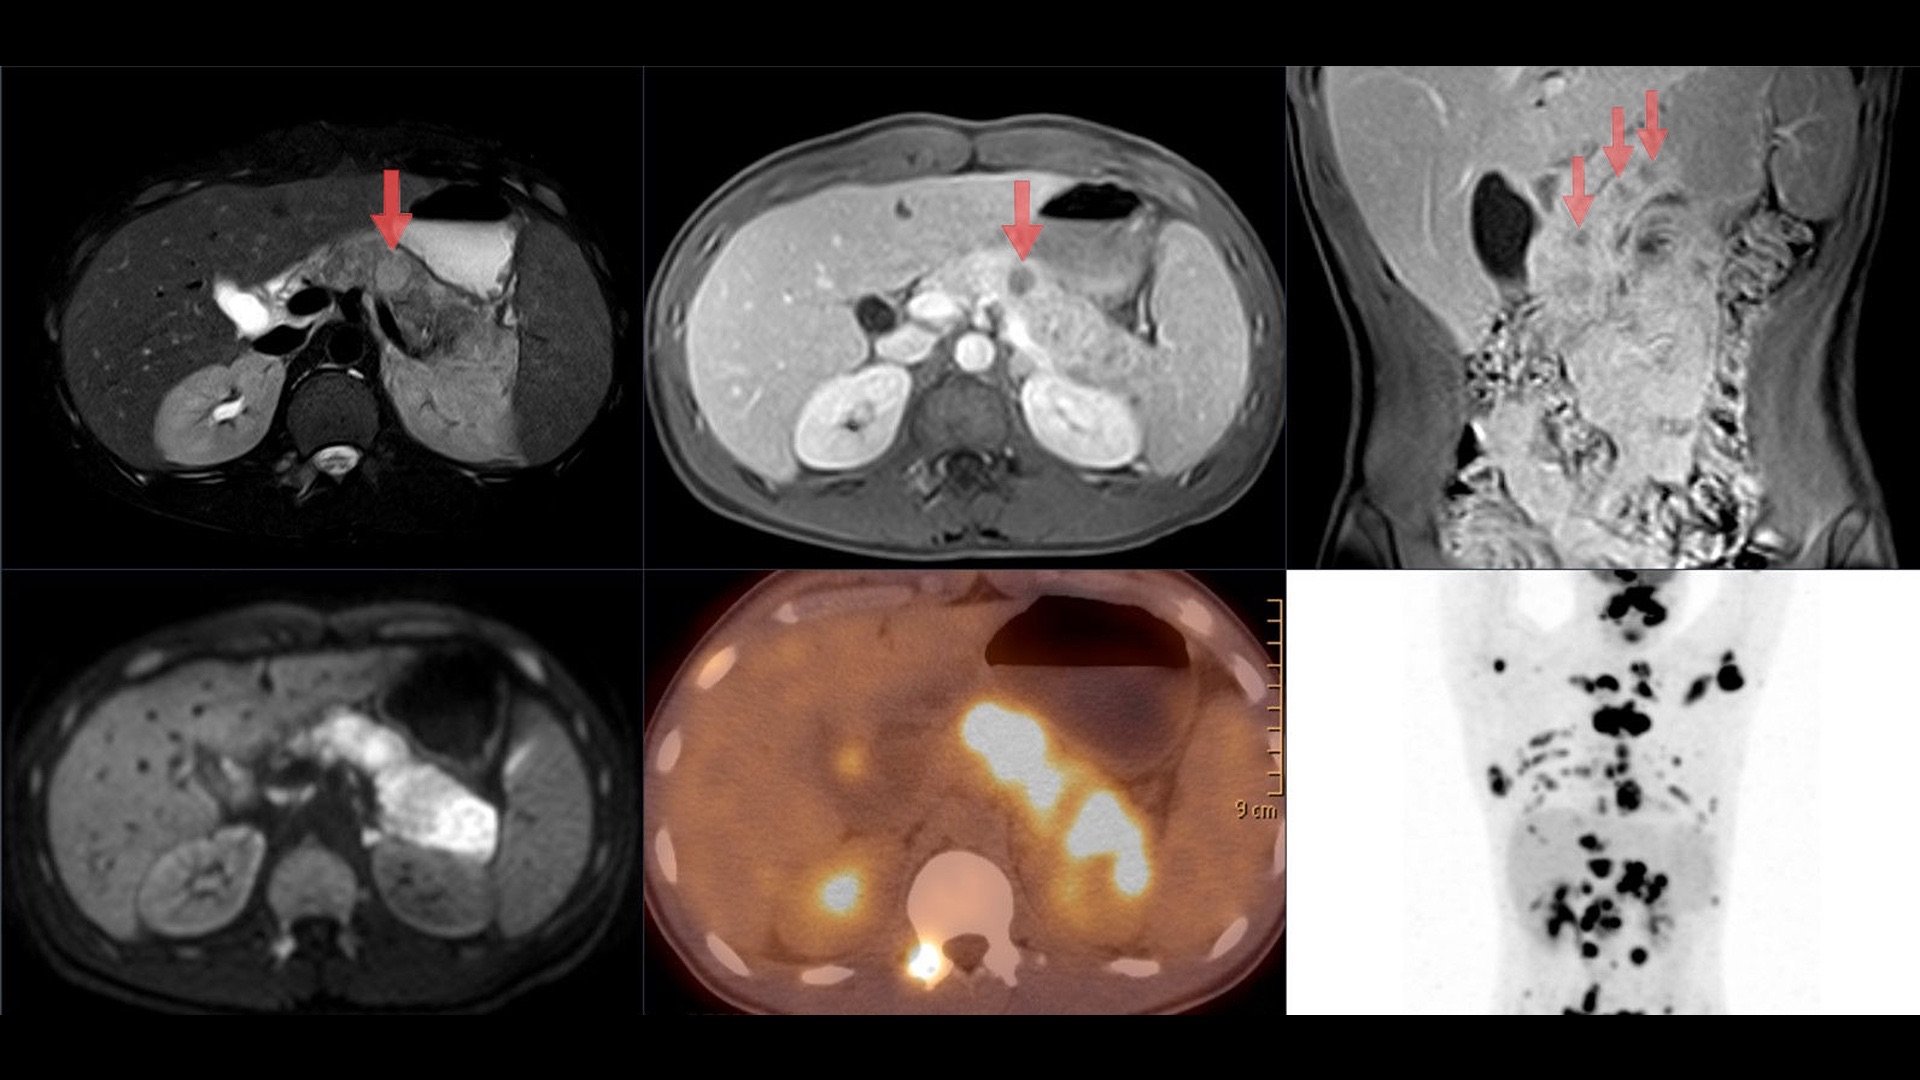

Die Non Hodgkin Lymphome umfassen eine heterogene Gruppe von B- und T-Zell Lymphomen (Tumore).

Die Non Hodgkin Lymphome unterteilen sich in 4 Kategorien. Diese umfassen niedrigmaligne (indolente) Typen (die alten Herren) und hochmaligne (aggressive) Typen (kleine, aggressive Kinder). Man unterscheidet außerdem NHL der B- oder T-Zellreihe (Babys oder Teetassen).